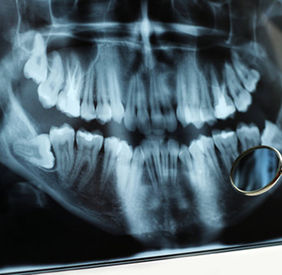

Root canal treatment in Ahmedabad is simply referred to as a “root canal.” It is a common dental procedure to treat infection at the centre of a tooth (the pulp). This RCT treatment helps save a tooth that might otherwise need to be extracted. While the phrase “root canal” may cause anxiety for some, the procedure itself is highly effective, generally painless with modern techniques, and essential for maintaining oral health. This essay explores the anatomy of a tooth, causes of pulp infection, the process of painless root canal treatment, its benefits, aftercare, and common misconceptions.